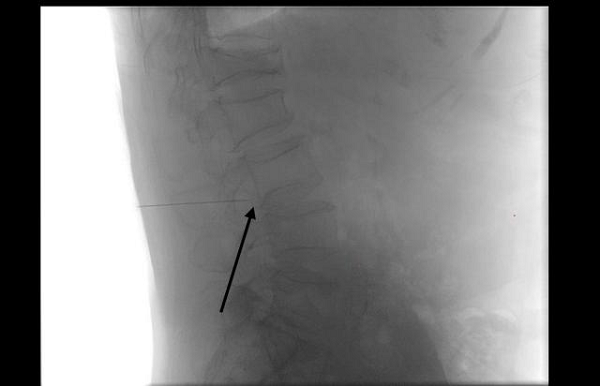

图:医生在影像引导下,精准定位病灶